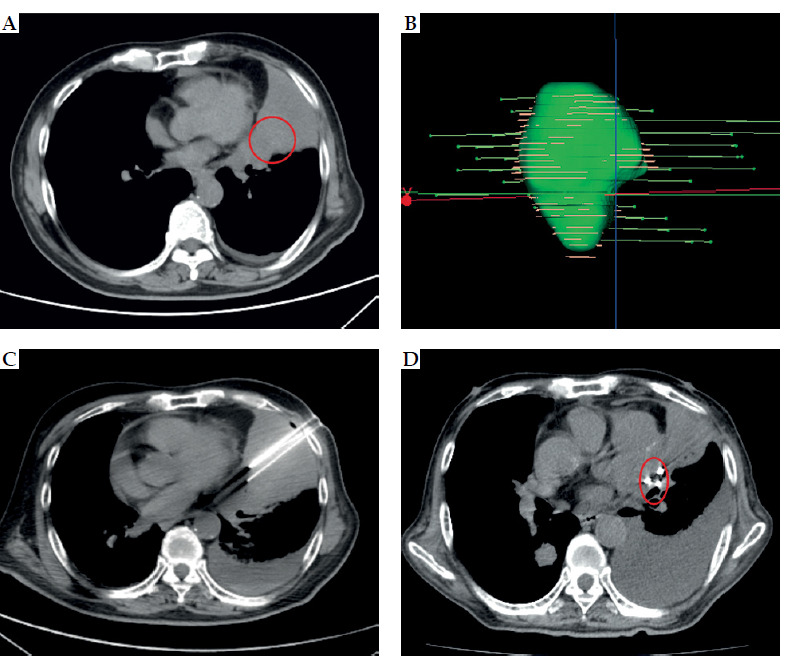

Purpose: This study aimed to explore the risk factors associated with difficult-to-control pain (visual analog scale [VAS] score > 3) experienced by patients with advanced non-small cell lung cancer (NSCLC) assessed at two months after receiving iodine-125 (125I) radioactive seed implantation combined with chemotherapy, in order to improve pain management and enhance patient quality of life.

Material and methods: A total of 87 patients diagnosed with advanced NSCLC were included in the study, all of whom underwent treatment using 125I radioactive seed radiotherapy and chemotherapy. Through univariate and multivariate analyses, the risk factors affecting pain control at two months post-treatment were identified. Predictive and survival analyses were done using ROC curves and Kaplan-Meier survival curves.

Results: The results indicated that minimal pleural distance, smoking history, and pleural effusion were independent risk factors influencing the control of pain shown in VAS scores. Moreover, a non-linear relationship between minimal pleural distance and difficulty of pain control was observed, indicating that the risk of uncontrolled pain decreases when the minimal pleural distance reaches ≥ 10.84 millimeters. ROC curve analysis demonstrated that the predictive capability of minimal pleural distance was the highest.

Conclusions: Minimal pleural distance, smoking history, and pleural effusion are significant factors in predicting the difficulty of pain control in patients with advanced NSCLC receiving 125I radioactive seed implantation combined with chemotherapy at two months post-treatment. Patients with a minimal pleural distance of less than 10.84 millimeters are more likely to experience uncontrolled pain after treatment. Therefore, developing predictive models may assist clinicians in more accurately evaluating treatment efficacy and patients' pain management needs.